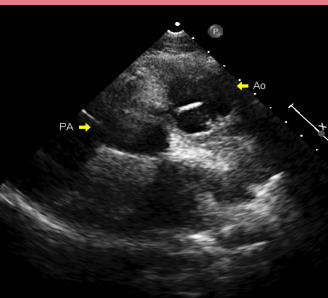

What is this an image of?

CC-TGA:

AO is ANTERIOR and to the LEFT of PA

CC TGA Fetal ECHO